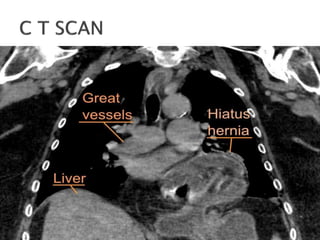

 This typeof hernia occurs when part of the stomach pushes through the diaphragm. The diaphragm normally has a small opening for the esophagus. This opening can become the place where part of the stomach pushes through. Small hiatal hernias can be asymptomatic (cause no symptoms), while larger ones can cause pain and heartburn.